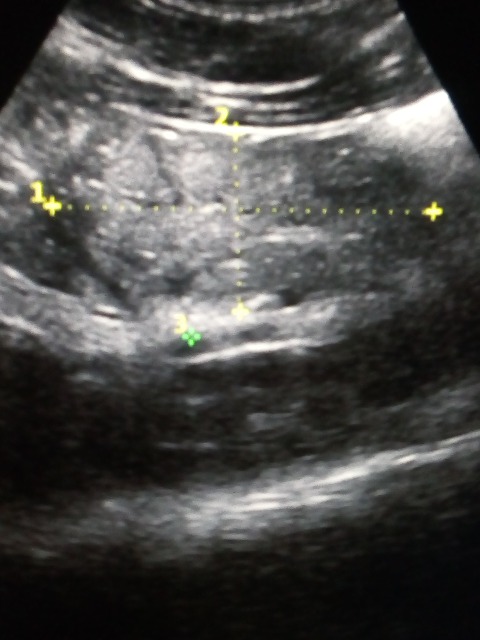

В 2012 году нефрэктомия слева по поводу рака почки. В течение пяти лет УЗИ без особенностей. Видео к сожалению нет, есть здесь на ваш взгляд образование в ложе почки или нет, такая форма не во всех срезах, в некоторых просто бесформенная масса. Не может ли кишечник накладываться на изображение, смотрела со спины. И может есть какая-то литература по рецидивам после нефрэктомии, как выглядят на УЗИ.